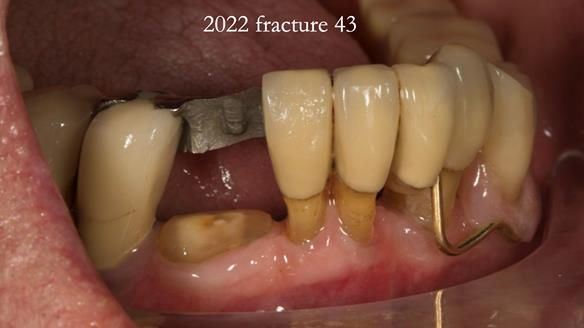

In 2022, tooth 43 fractured.

An artificial tooth was added to the RPD

by welding a cobalt–chrome tag to the bar

and adding the tooth.

The denture continued to function extremely well.

This case was always about function, not aesthetics.

Ken’s teeth were never going to look perfect.

There were stained composites, old restorations, and obvious wear.

That was accepted from the outset.

The way Rowan lengthened the teeth — particularly in the upper RPD — to match the existing gingival recession on the remaining teeth was superb. The dentures sit naturally within the context of the rest of the mouth.